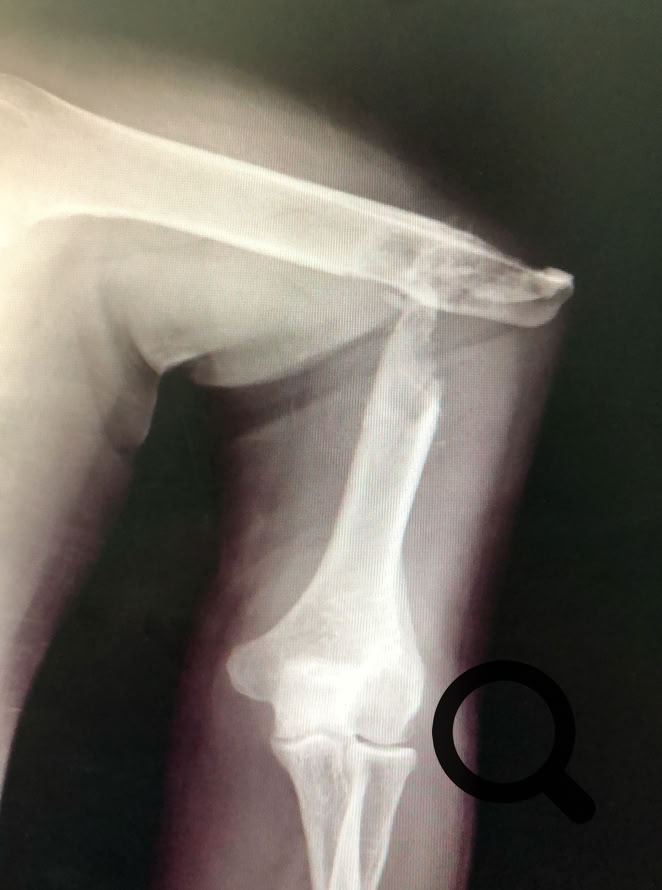

Como no podía ser de otra manera porque nos pasa siempre, nos hemos enfrentado a cirugía de alta complejidad, pseudoartrosis de húmero, fémur y tibia en adultos, así como  fracturas complejas.

Una cosa queda clara, los “masajes tradicionales cameruneses“ no son efectivos en el tratamiento de las fracturas de cualquier hueso, tanto en niños como en adultos y conducen inevitablemente a pseudoartrosis  muy difíciles de tratar.